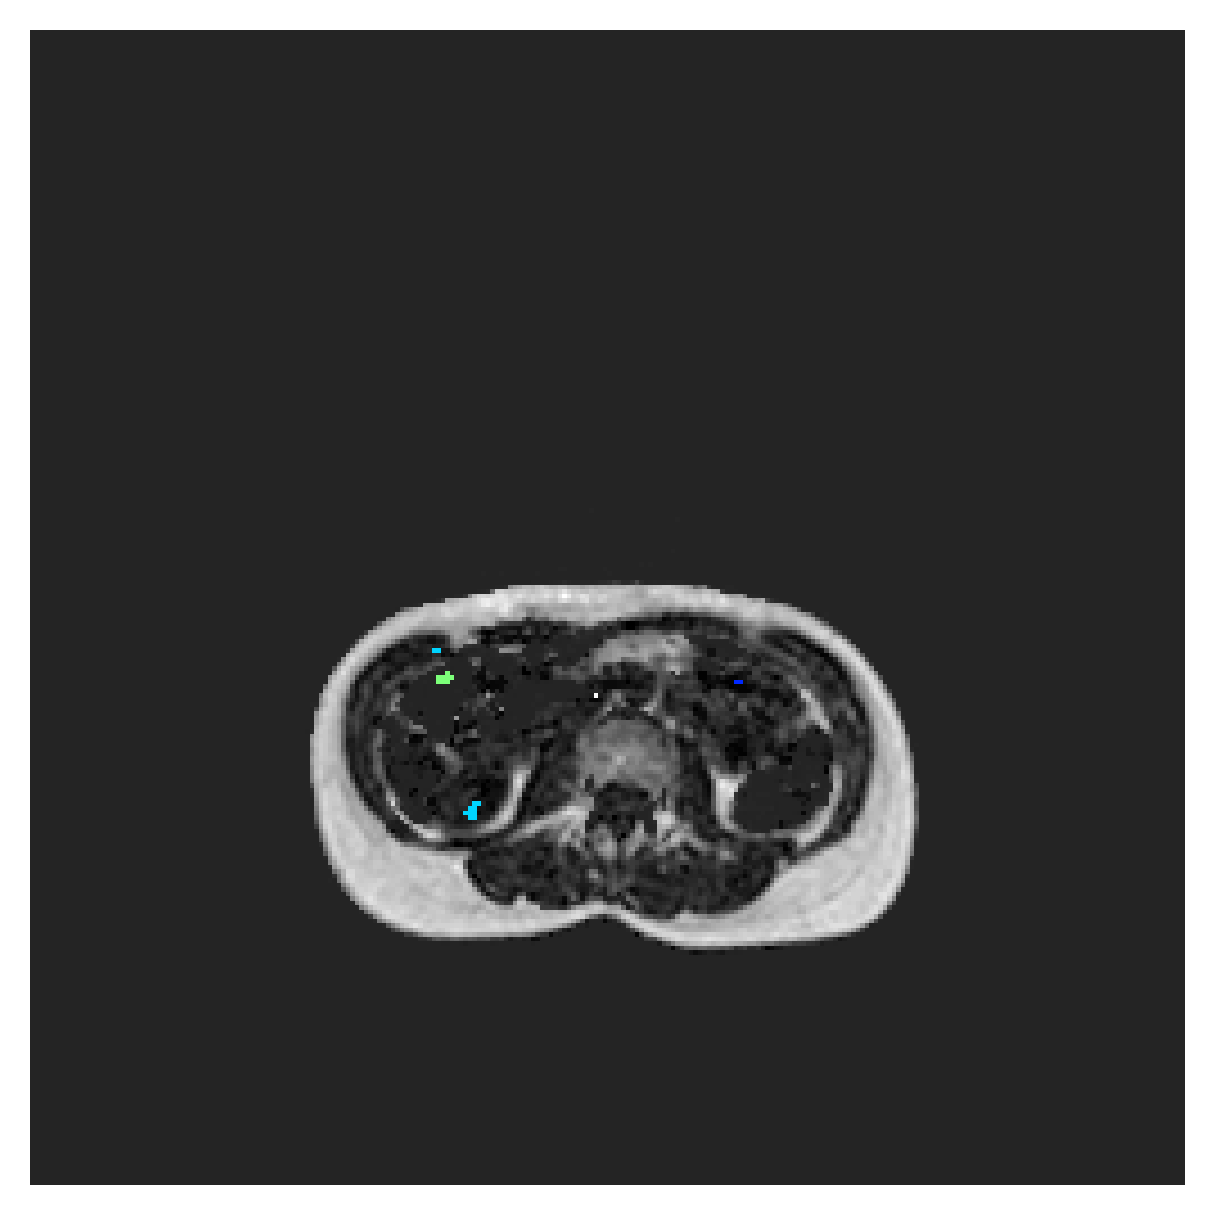

5.2 Abdominal organ segmentation

Using 2D distance maps

In Table 3, the average DSC and HD95 results are shown (both using 2D and 3D distance maps) for the task of abdominal organ segmentation in POEM data (for boxplots see figures 8 and 9). We see that training with and (with distances calculated on 2D slices) performs comparably, while using and produces lower scores in both DSC and HD95 metric. On this dataset, the CRF-loss is able to compete with the boundary loss-based training strategies, even outperforming them on most classes. Most notably, all models trained with boundary loss appear to have a hard time segmenting the liver. We hypothesize this may be due to extremely severe class imbalance, as the liver covers a very large area compared to the rest of the classes. It is thus also more strongly affected by undersegmentations.

According to the validation curves in Figure 7, training on this dataset is less stable, and slower, than on the ACDC one, for all methods. Using Euclidean or MBD maps appears to reach full-supervision scores, while the other methods lag behind. However, due to the long computation times on 3D data from the POEM cohort, these curves now show the evolution of the 2D Dice, which is less representative of the true success of the methods.

Using 3D distance maps

Inspecting the values of training with on distance maps computed in 3D from Table 3, we notice that the results generally improve over values achieved by using 2D distance maps. Most notable decreases are visible in HD95 values, as using volume-calculated distance maps provides more global information and additionally penalizes spatially unreasonable segmentations. The methods based on are now able to compete with the CRF-loss, in particular the one.

In Figure 10, the validation curve evolution is plotted. Comparing it to the one with using 2D-computed distance maps, in Figure 7, we see that the curves for all the methods training with improve, with the exception of based one. The lack of improvement here could be attributed to the MBD bleeding through object boundaries (due to noise) and propagating low distances further away in the volume, causing under-penalization. This is also suggested by the degradation in performance from 2D to 3D maps in Table 3. But at the same time, it allows for better segmentation of large and/or elongated (homogeneous) objects, which is also confirmed by the large improvement of liver segmentation scores in Table 3.

5.2.1 Qualitative comparison

In Figure 11 and 12 we show the same random slices in cases of calculating the boundary loss on 2D- and 3D-based distances, respectively. Comparing the two figures again indicates that the intensity-aware distances offer most improvement when calculated in 3D over 2D. The exception here is the MBD, which seems to even slightly degrade for most classes.